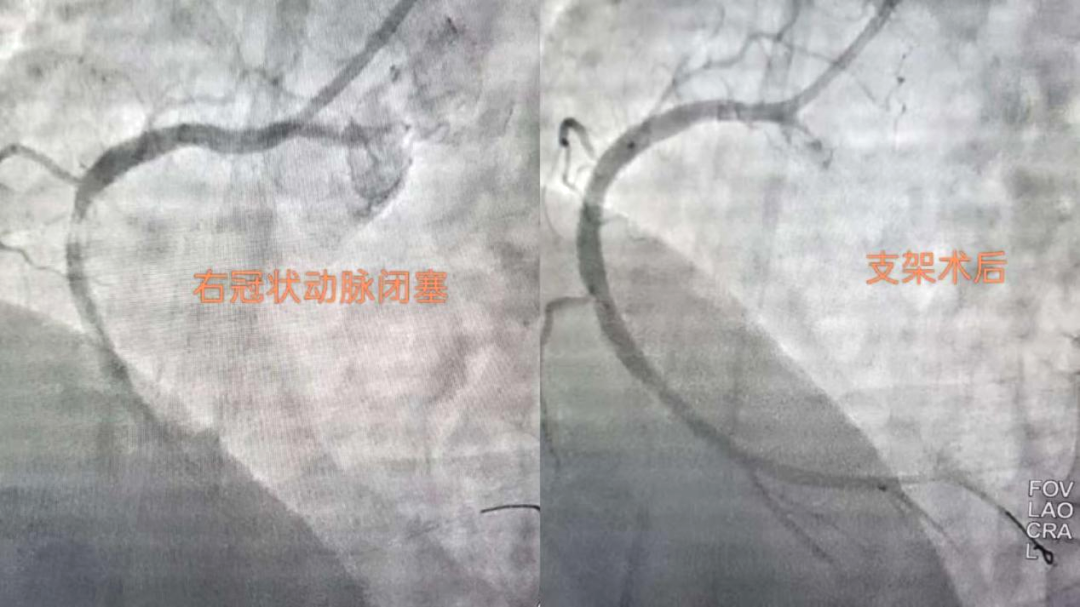

搶時間就是搶生命!06:46穿刺,06:47成功,06:49冠脈造影明確:右冠狀動脈中段完全閉塞。導(dǎo)絲迅速通過,支架精準(zhǔn)植入,07:03血流恢復(fù),手術(shù)成功結(jié)束。患者胸痛明顯緩解,生命體征趨于平穩(wěn)。從入院到血管再通,不到兩小時。